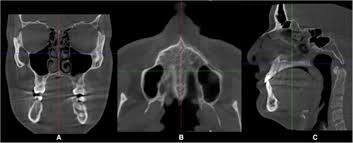

그러나 수술을 피하고 싶은 대중들의 마음에 SARPE보다는 효과가 떨어지지만 대략 70~80%의 효과는 낼수 있는 미니스크류를 이용한 확장장치가 나온 것입니다.

이젠 손잡이를 바꾸어야합니다(어금니-> 미니스크류)

좌우측 구개골을 벌리는 데 있어 상악어금니보다 더 강력한 손잡이가 필요합니다.

바로 입천장의 구개골에 직접 미니스크류를 식립하여 윗턱을 벌리는 손잡이로 쓰는 것입니다.

이것을 MARPE라고 부릅니다.

보통 20세 이하일수록 성공률이 높고 20세 중후반까지 성공률 80%를 보인다고 보고하고 있습니다.